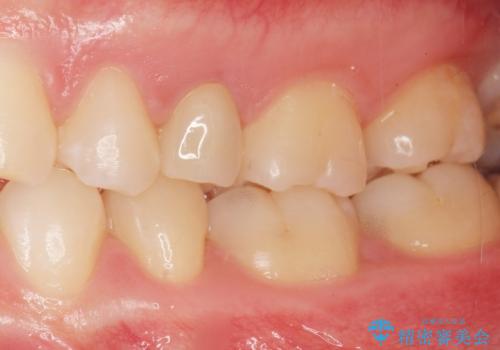

自然な仕上がりにご満足頂けました。

「うわー、自分の歯みたい!すごい!」と喜んで下さいました。

以前つけた被せ物は1週間でとれてしまったそうで、歯ぎしりのご自覚もあることから、咬み合わせの調整を丁寧に行いました。

仮歯およびクラウンの仮付け期間を設け、はずれにくいことや咬み合わせに問題がないことを確認した上で本付けを行いました。

クラウンの種類:オールセラミッククラウン スタンダード